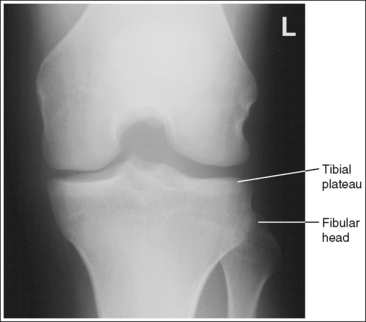

The knee demonstrates an AP projection. The medial and lateral femoral epicondyles are in profile, the femoral condyles are symmetrical, the intercondylar eminence is centered within the intercondylar fossa, and the tibia is superimposed over 0.25 inch (0.6 cm) of the fibular head.

• To obtain an AP knee projection, place the patient in a supine position with the knee fully extended. Internally rotate the leg until an imaginary line drawn between the medial and lateral femoral epicondyles is positioned parallel with the IR (Figure 6-71). This positioning places the medial and lateral femoral epicondyles at equal distances from the IR as well as medially and laterally in profile, respectively. It also centers the intercondylar eminence within the intercondylar fossa and draws the fibular neck and a portion of the fibular head from beneath the tibia.

• Effect of rotation. If the femoral epicondyles are not positioned parallel with the IR, an AP projection has not been obtained. If the patient's leg was not internally rotated enough to place the epicondyles at equal distances from the IR, they are not in profile, the medial femoral condyle appears larger than the lateral condyle, and the tibia is superimposed over more than 0.25 inch (0.6 cm) of the fibular head (see Image 54). If the patient's leg was internally rotated more than needed to place the femoral epicondyles at equal distances from the IR, the epicondyles are not demonstrated in profile, the lateral femoral condyle appears larger than the medial condyle, and the tibia is superimposed over less than 0.25 inch (0.6 cm) of the fibular head (see Image 55).

The knee joint space is open, the anterior and posterior condylar margins of the tibia are superimposed, the intercondylar eminence and tubercles are demonstrated in profile, and the fibular head is demonstrated approximately 0.5 inch (1.25 cm) distal to the tibial plateau.

• The anterior and posterior condylar margins of the tibia are superimposed if the correct central ray angulation, as determined by the patient's upper thigh and buttocks thickness, is used. By studying the tibial plateau region, you will see that the tibial plateau slopes distally approximately 5 degrees from the anterior condylar margin to the posterior condylar margin on both the medial and lateral aspects (Figure 6-72). Only if the central ray is aligned parallel with the tibial plateau slope is an open knee joint space obtained.

• Determining the central ray angulation. When a patient is placed in a supine position, the degree and direction of the central ray angulation required depend on the thickness of the patient's upper thigh and buttocks. This thickness determines how the lower leg and the tibial plateau align with the IR. Figure 6-73 shows a guideline that can be used to determine the central ray angulation for different body sizes; it illustrates the relationship of the tibial plateau to the imaging table as the patient's upper thigh thickness increases. Note that a decrease occurs in femoral decline, and a shift occurs in the direction of the tibial plateau slope as the thickness of the thigh decreases. Because of this plateau shift, the central ray angulation must also be adjusted to keep it parallel with the plateau and to achieve an open knee joint. For optimal AP knee projections, measure from the patient's anterior superior iliac spine (ASIS) to the imaging table on either side to determine the central ray angulation to use for each knee examination. When measuring this distance, do not include the patient's abdominal tissue. Keep the calipers situated laterally next to the ASIS. If the measurement is less than 18 cm, a 5-degree caudal angle should be used. If the measurement is 19 to 24 cm, a perpendicular beam should be used. If the measurement is greater than 24 cm, a 5-degree cephalad angle should be used. Using the correct central ray angulation not only results in an open knee joint space but also provides optimal demonstration of the intercondylar eminence and tubercles without foreshortening.

• Effect of poor central ray angulation. When examining an AP knee projection for which an inaccurate central ray angulation was used, you can determine how to adjust the angulation by judging the shape of the fibular head and its proximity to the tibial plateau. If the fibular head is foreshortened and demonstrated more than 0.5 inch (1.25 cm) distal to the tibial plateau, the cephalad angle was too great (see Image 58). If the fibular head is elongated and demonstrated less than 0.5 inch (1.25 cm) distal to the tibial plateau, the caudad angle was too great (see Image 59).

• Center the central ray to the midline of the knee at a level 1 inch (2.5 cm) distal to the palpable medial epicondyle to place the knee joint in the center of the exposure field. (As long as the knee remains extended, an alternative central ray placement is 0.5 inch (1.25 cm) distal to the patellar apex.) Open the longitudinal collimation enough to include one fourth of the distal femur and proximal lower leg. Transverse collimation should be to within 0.5 inch (1.25 cm) of the knee skin line.

The femoral epicondyles are not in profile, the medial femoral condyle appears larger than the lateral condyle, and the fibular head demonstrates more than 0.25 inch (0.6 cm) of tibial superimposition. The leg was externally rotated.

Internally rotate the leg until the femoral epicondyles are at equal distances from the IR.

The femoral epicondyles are not in profile, the lateral femoral condyle appears larger than the medial condyle, and the fibular head demonstrates less than 0.25 inch (0.6 cm) of tibial superimposition. The leg was internally rotated.

Externally rotate the leg until the femoral epicondyles are at equal distances from the film.